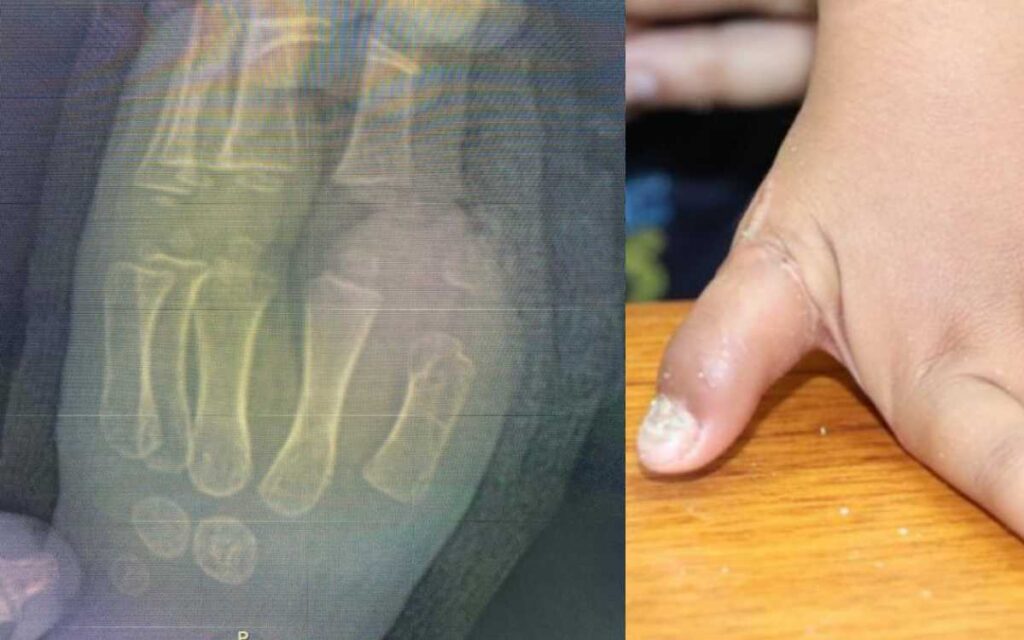

Para reimplantarlo, el equipo de Cirugía Plástica reconstructiva del Hospital de Traumatología y Ortopedia, encabezado por el doctor Miguel de la Parra Márquez, tuvo que unir arterias, venas, tendones, hueso y nervios con suturas milimétricas, lo que implicó un proceso quirúrgico de alta complejidad.

El procedimiento, llamado supramicrocirugía, se realizó con el uso de microscopio al máximo aumento, las suturas fueron ultrafinas con un hilo transparente y tan delgado que prácticamente flota en el aire.

El trabajo quirúrgico duró seis horas y se realizó contra reloj, pues el miembro desprendido se encontraba en una hielera, envuelto en gasas húmedas, entre agua y hielo para su preservación por un tiempo máximo de 24 horas.